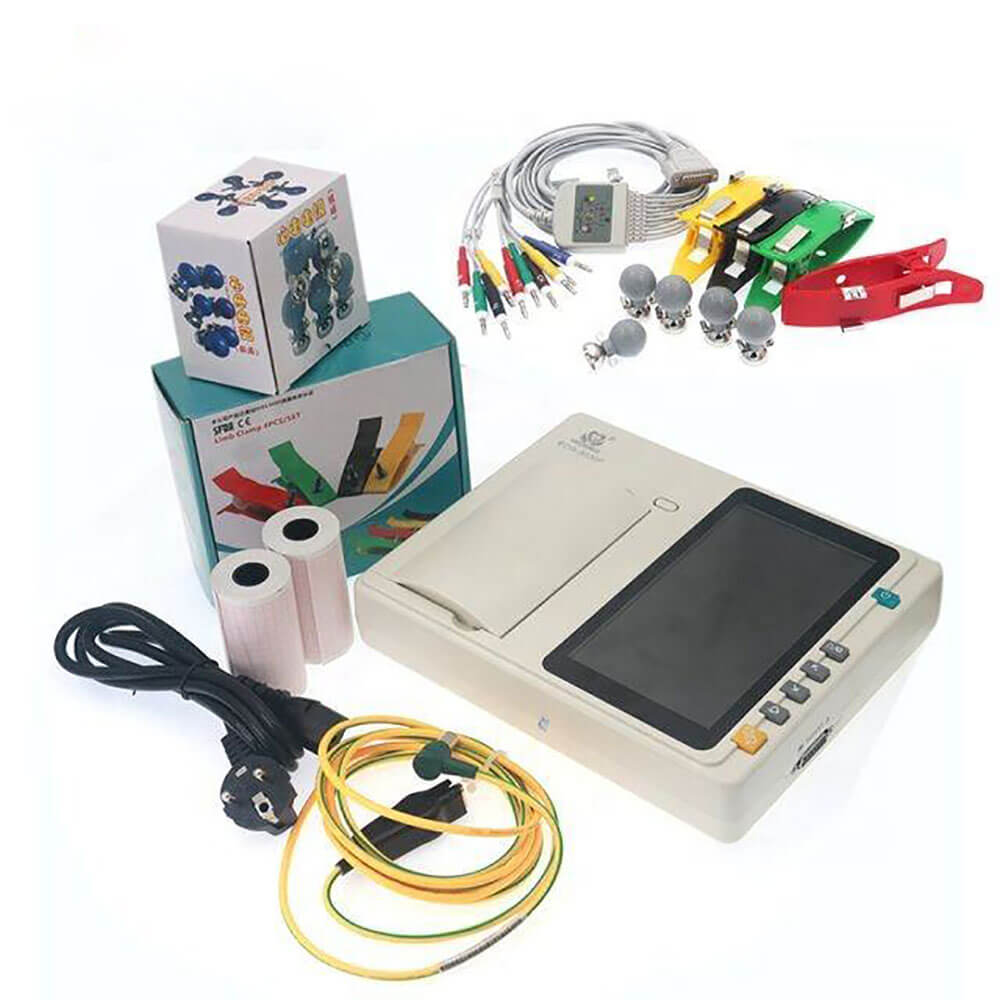

Technical Specification (1)Different applications based on Digital Pre Programs (2)A current module of 4-channel E ....

CONTEC ECG600G Digital 6 channel Electrocardiograph ECG machine EKG CE

CONTEC ECG600G Digital 6 channel Electrocardiograph ECG machine EKG CE

CONTEC ECG300G Electrocardiograph

CONTEC ECG300G Electrocardiograph

ECG 1200G – Contec

ECG 1200G – Contec

ECG 1212G – Contec

ECG 1212G – Contec

YKD MED ECG 3 CHANNEL

YKD MED ECG 3 CHANNEL

CONTEC ECG MACHINE

CONTEC ECG MACHINE